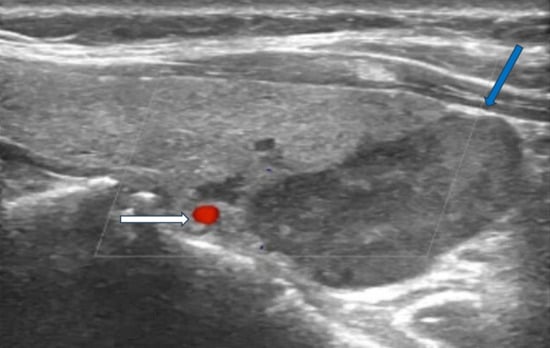

Sonographic features indicative of PC typically include lesion size greater than 3 cm, substantially larger than typical benign adenomas, which generally measure 1–2 cm. Malignant lesions often exhibit irregular or lobulated margins with evidence of invasion into adjacent tissues, in contrast to the smooth, well-circumscribed borders characteristic of benign counterparts (Figure 1).

Figure 1. Ultrasonography image of parathyroid carcinoma. Legend: 65-year-old patient with parathyroid carcinoma presented with serum PTH of 1300 pg/mL (12–88 pg/mL) and Ca:13 mg/dL (8.8–10.6 mg/dL). Ultrasonography showed a hypoechoic mass with lobulated borders (32 × 23 × 14 mm) next to the lower pole of the left thyroid lobe (blue arrow). The white arrow shows the inferior thyroid artery.

Additional suspicious findings include a heterogeneous echotexture with marked hypoechogenicity, reflecting necrosis, hemorrhage, or fibrosis, and a depth-to-width ratio of ≥1, as malignant lesions tend to be taller than wide. The presence of intralesional calcifications and cervical lymphadenopathy further strengthens the suspicion for carcinoma [2,15,16] (Figure 2).

Figure 2. Ultrasonography images of parathyroid carcinoma neck metastases. Legend: 70-year-old patient presented with parathyroid carcinoma lymph node metastases with hypoechoic lesions without fatty hilum ((A), white arrow) and chaotic blood flow in Doppler imaging ((B), white arrow).